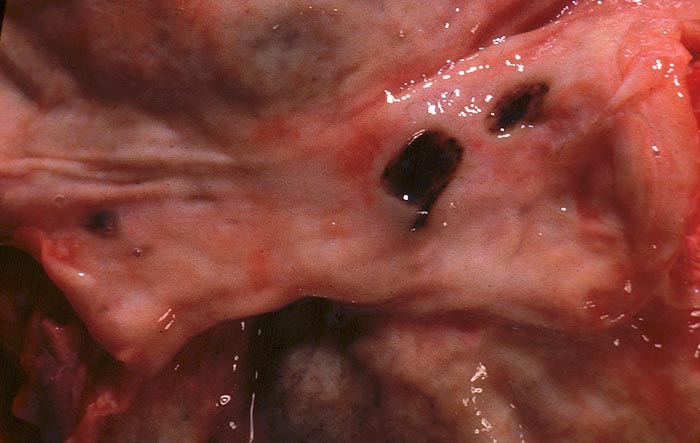

PathoPic ID 754 - Frische präpylorische Ulzera

Frische präpylorische Ulzera

Magen

Scharf begrenzte leicht eingesenkte mit hämatinisiertem Blut belegte Ulzera.

Pneumonie.